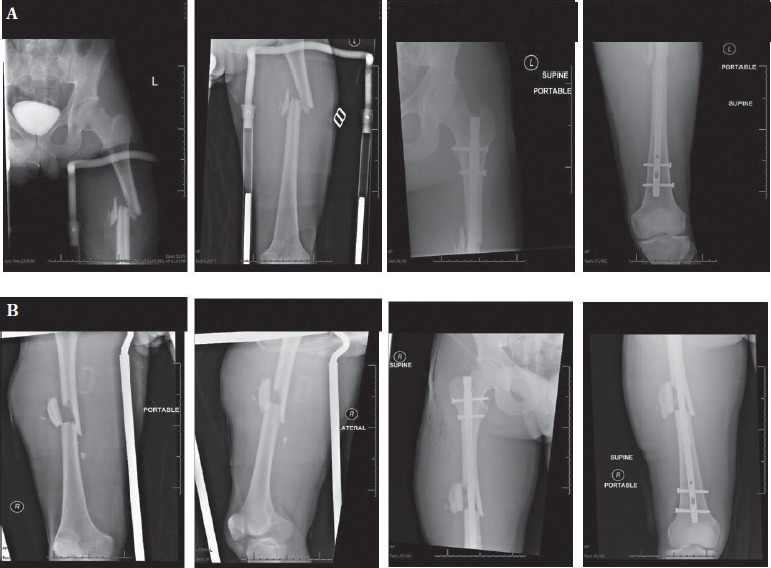

Over the first 24 hours, the patient remained lucid. On hospital day (HD) 1, the patient underwent definitive fixation with bilateral femoral intramedullary nails. After intubation the patient was placed in the lateral decubitus position and a piriformis start point was used for nail entry bilaterally. Both femurs were sequentially reamed using flexible reamers to 10.5-mm, and then 9-mm diameter antegrade nails with proximal and distal locking screws were placed [Figure 1]. The left olecranon fracture was also fixed with open reduction and internal fixation by a second surgical team during fixation of the left femur. Total operative time was four hours and ten minutes and the patient had 500cc of blood loss. In order to closely monitor ventilatory and oxygenation status post-operatively, the patient remained intubated following the procedure and returned to the SICU. Shortly after arriving to the intensive care unit, nursing documented a normal mental status exam.

Figure 1. Preoperative and post-operative films of the left femur (A) and right femur (B). Both femurs were definitively fixed with Synthes 9mm diameter titanium anterograde intramedullary nails and locking screws.